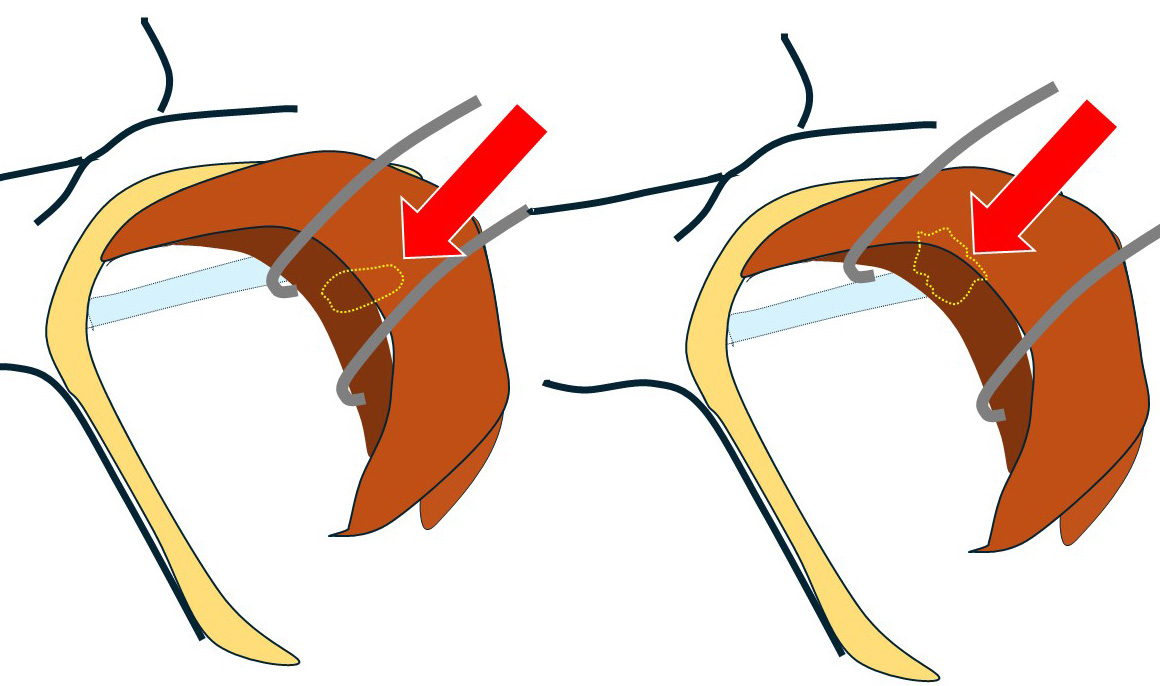

通常の腋窩郭清(小胸筋内縁まで)の視野です。

鎖骨下リンパ節(レベルⅢ)は「小胸筋の向こう(奥)」にあるので『小胸筋を何とかしなくては』そこへはアプローチできません。

殆ど(ほぼ全て)の乳腺外科医は、ここまでで(小胸筋を何ともすることもできず)終了となります。

〇この先が「鎖骨下郭清」となります。

通常であれば

このように… 小胸筋にテーピングをして

手前に引っ張り出せば図左のように鎖骨下リンパ節が「ばっちり」鎖骨下静脈と離れて認識できます。

これ(向かって左の図)が「コラム 540回目症例」であり、それであれば「何てこともない」のですが…

向かって右に見える「今回の症例」は(小胸筋を引っ張っても)節外浸潤した鎖骨下リンパ節が(エコーで想像した通り)鎖骨下静脈に(恋人たちのように)ぴったりと寄り添って離れない!

鎖骨下リンパ節が鎖骨下静脈から外せない。この視野で無理やり剥がそうとすれば…(考えたくもない)